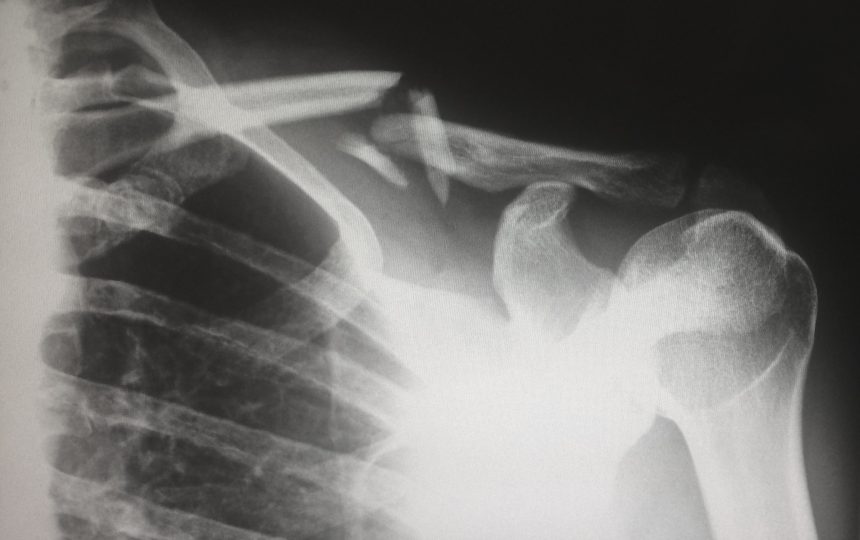

A osteoporose pode ser identificada por um exame de densitometria óssea e radiografia, que avaliam a densidade dos ossos e músculos do corpo, podendo identificar quando eles estão muito finos ou então quando a perda está no estágio inicial.

As lesões mais comuns são as fraturas das vértebras por compressão, que levam a problemas de coluna e à diminuição da estatura.

Também são relevantes e comuns as fraturas do colo do fêmur, punho (osso rádio) e costelas. A dor costuma ser no local traumatizado.